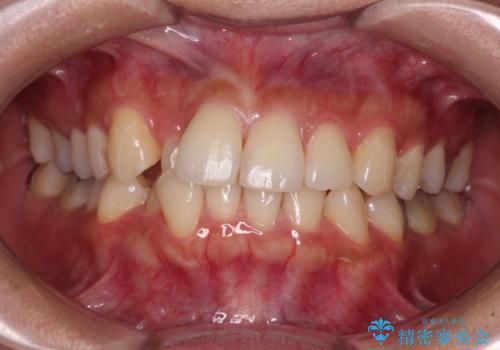

捻れて前に出ている前歯 ワイヤー装置での非抜歯矯正